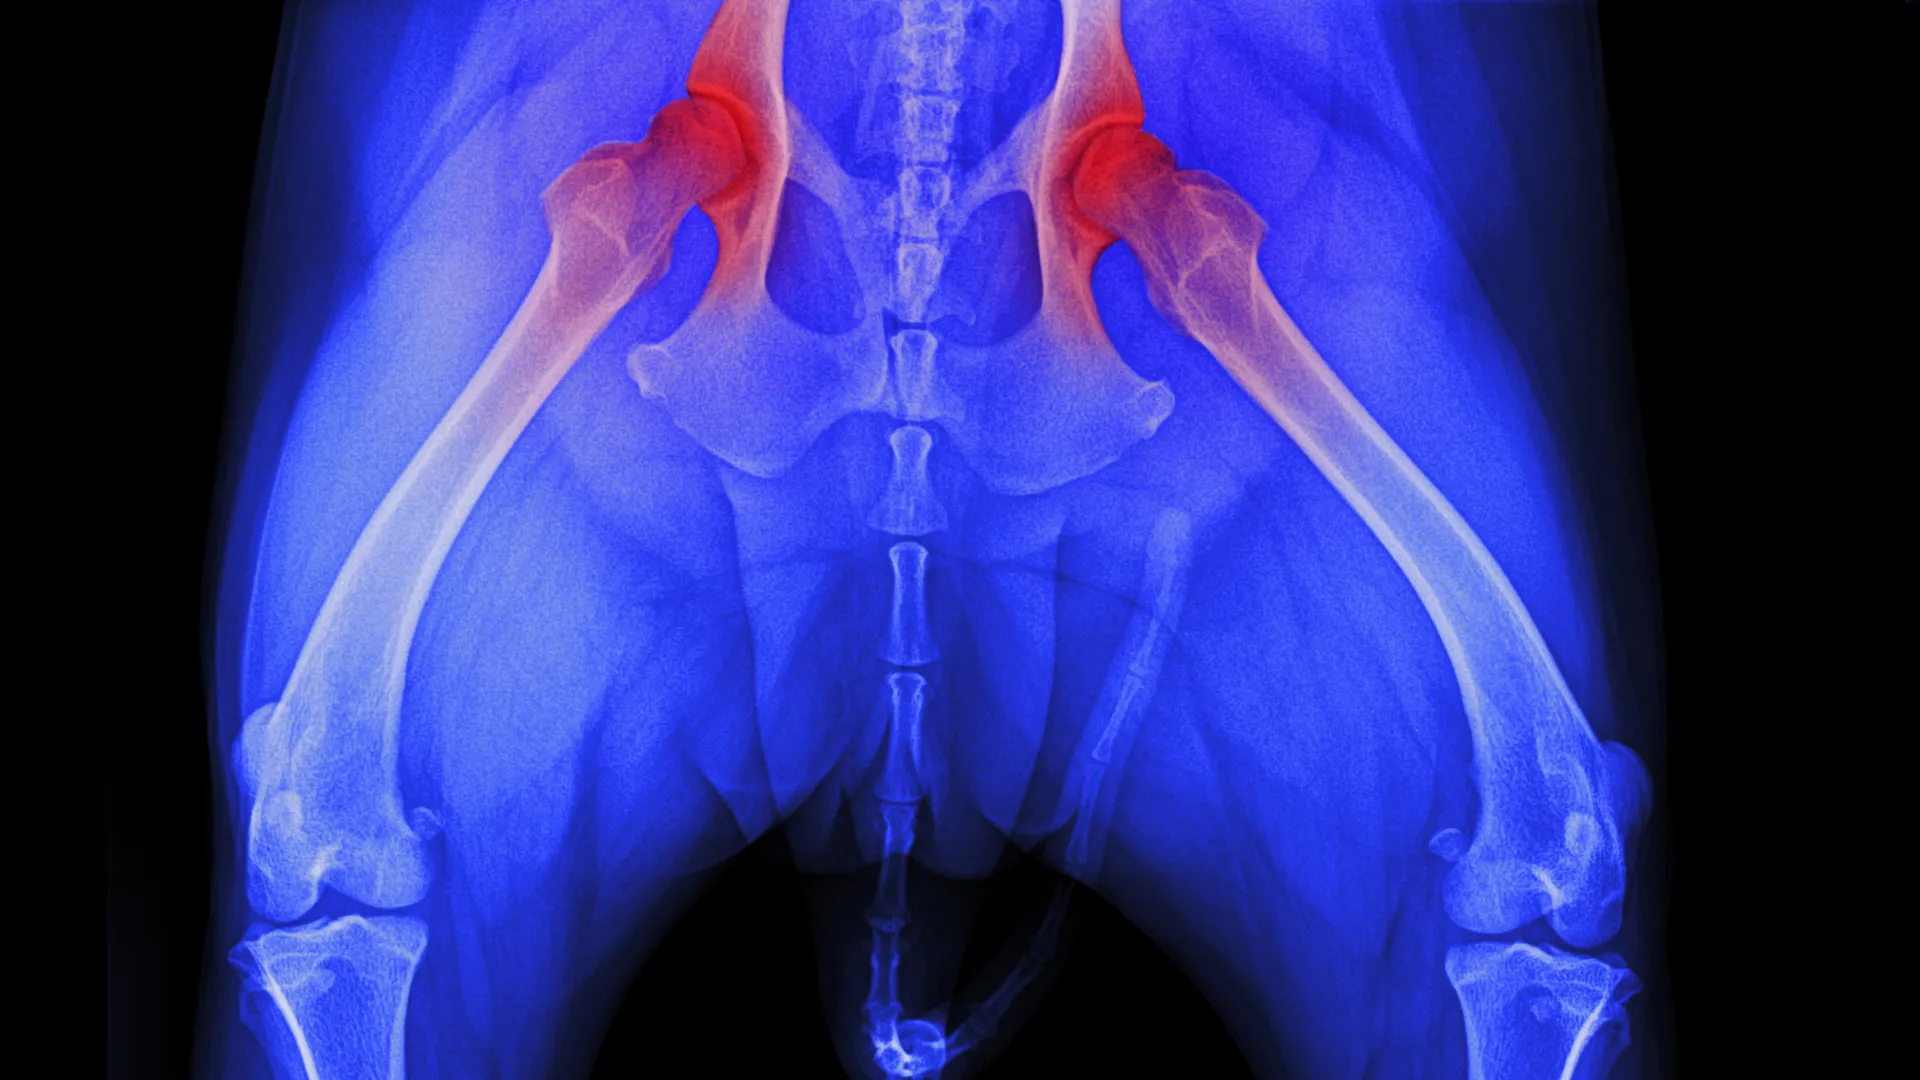

X-Rays (Radiographs)

X-rays are the main way to confirm hip dysplasia. Your dog will need to be sedated so the vet can position the legs correctly. They use extended-leg views to see how well the hip joint fits together.

OFA Certification

The Orthopedic Foundation for Animals (OFA) is the standard certification system in the United States. Here is how it works:

| OFA Rating | What It Means |

|---|---|

| Excellent | Near perfect hips with deep sockets and tight fit |

| Good | Normal hips with minor imperfections |

| Fair | Passable hips with some concerns but still breedable |

| Borderline | Cannot determine if normal or dysplastic, needs recheck |

| Mild Dysplasia | Early signs of hip problems |

| Moderate Dysplasia | Clear hip problems with joint changes |

| Severe Dysplasia | Advanced hip problems with significant joint damage |

OFA certification requires dogs to be at least 2 years old, when the hips are fully developed. X-rays are submitted to OFA, where three board-certified veterinary radiologists review them and assign a rating.

PennHIP Evaluation

PennHIP is another hip screening method that measures joint laxity using a distraction index (DI). This can be done as early as 16 weeks old.

| Distraction Index (DI) | Risk Level |

|---|---|

| Less than 0.3 | Low risk of developing hip dysplasia |

| 0.3 to 0.7 | Moderate risk |

| Greater than 0.7 | High risk of developing hip dysplasia |

PennHIP can predict future hip problems earlier than OFA, giving you more time to start preventive care.